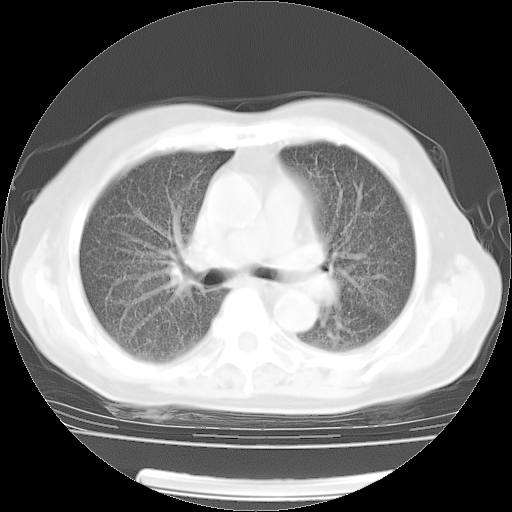

4月28日肺部CT——再次出现类似去年5月9日——透光度降低,(影像科认为)“间质性”改变。

4月28日肺部CT——再次出现类似去年5月9日——透光度降低,“间质性”改变。